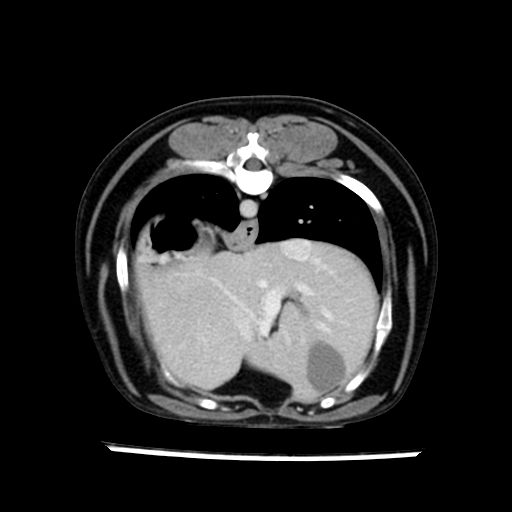

prescritto esame TAC

sequenza immagini limitata al fegato reni e surreni

le immagini ecografiche rispetto alla tac datano circa 7 mesi prima ,le surrenali sono normali nonostante il test acth sia risultato positivo .all’esame TAC dopo diversi mesi risultano aumentate armonicamente nel volume e si individua un forte sospetto di adenoma ipofisario .

sospetto adenoma ipofisario vs. meno probabilmente meningioma della base; intertiziopatia polmonare; lesione espansiva epatica, verosimilmente del lobo laterale sinistro, di sospetta natura neoplastica; lesioni spleniche di natura da definire; iperplasia/ipertrofia delle ghiandole surrenali, bilateralmente; vertebra di transizione del rachide toracico; tenosinovite cronica del muscolo bicipite brachiale di destra.